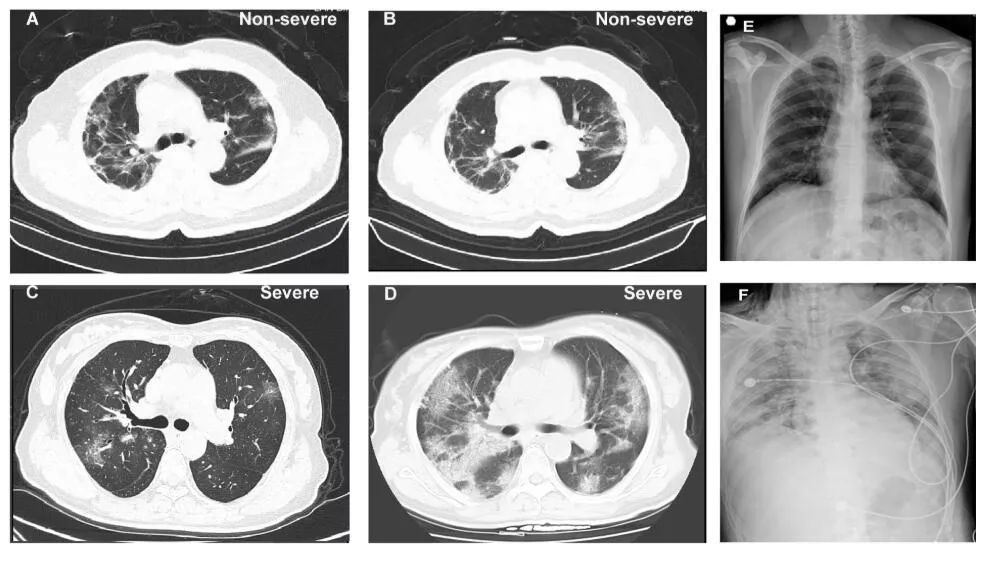

目前,核酸试剂盒检测仍为新冠病毒感染诊断的标准手段,而肺部CT检测也被列入湖北省的临床诊断标准。对于检测手段的争议,这篇论文也给出了相应的数据。论文指出,入院时,76.4%患者的肺部CT出现异常,其中最普遍的分别为肺部磨玻璃样阴影(50.0%)和肺部双侧斑样阴影(46.0%)。而23.9%的非重症患者和5.2%的重症患者在CT图像中未显现出异常,对于这部分患者,可以通过临床症状结合核酸试剂盒进行诊断。

非重症组与重症组的CT图像对比